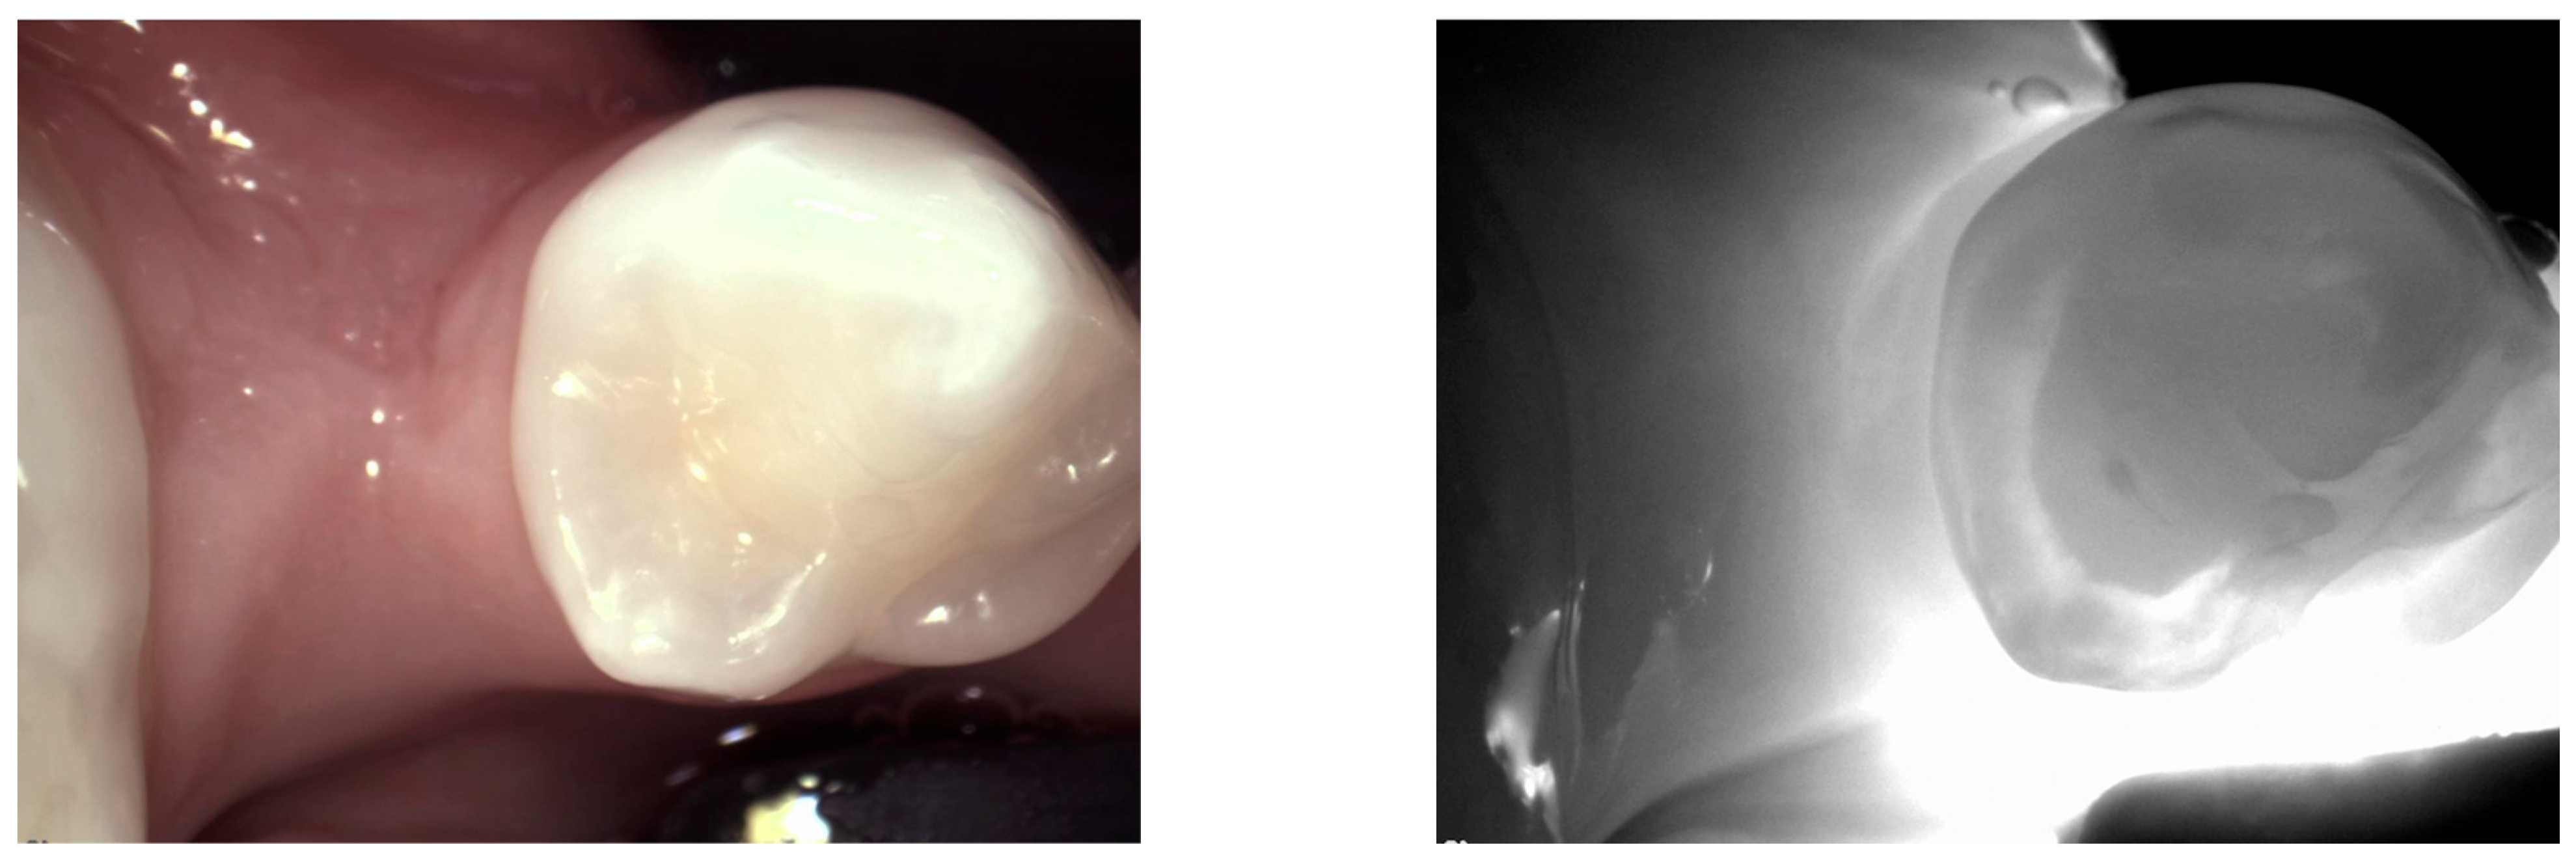

1. Healthy Teeth